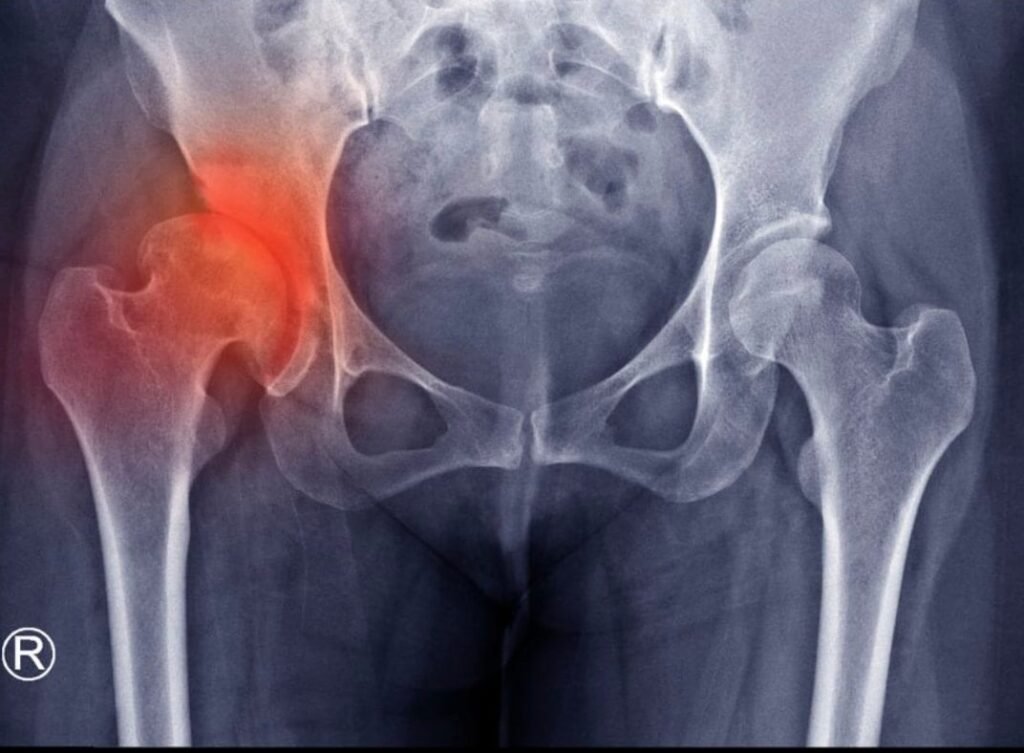

Στο κέντρο της άρθρωσης του ισχίου υπάρχει ένα στρώμα λείου χόνδρου που προστατεύει και απορροφά τους κραδασμούς καθώς τα οστά κινούνται. Όταν αυτός ο χόνδρος αρχίζει να λεπταίνει ή να φθείρεται, τα οστά τρίβονται μεταξύ τους, προκαλώντας πόνο, δυσκαμψία, φλεγμονή και τελικά μια κατάσταση γνωστή ως οστεοαρθρίτιδα του ισχίου (ή αλλιώς κοξάρθρωση).

Φωτογραφία: papoutsis-ortho.gr